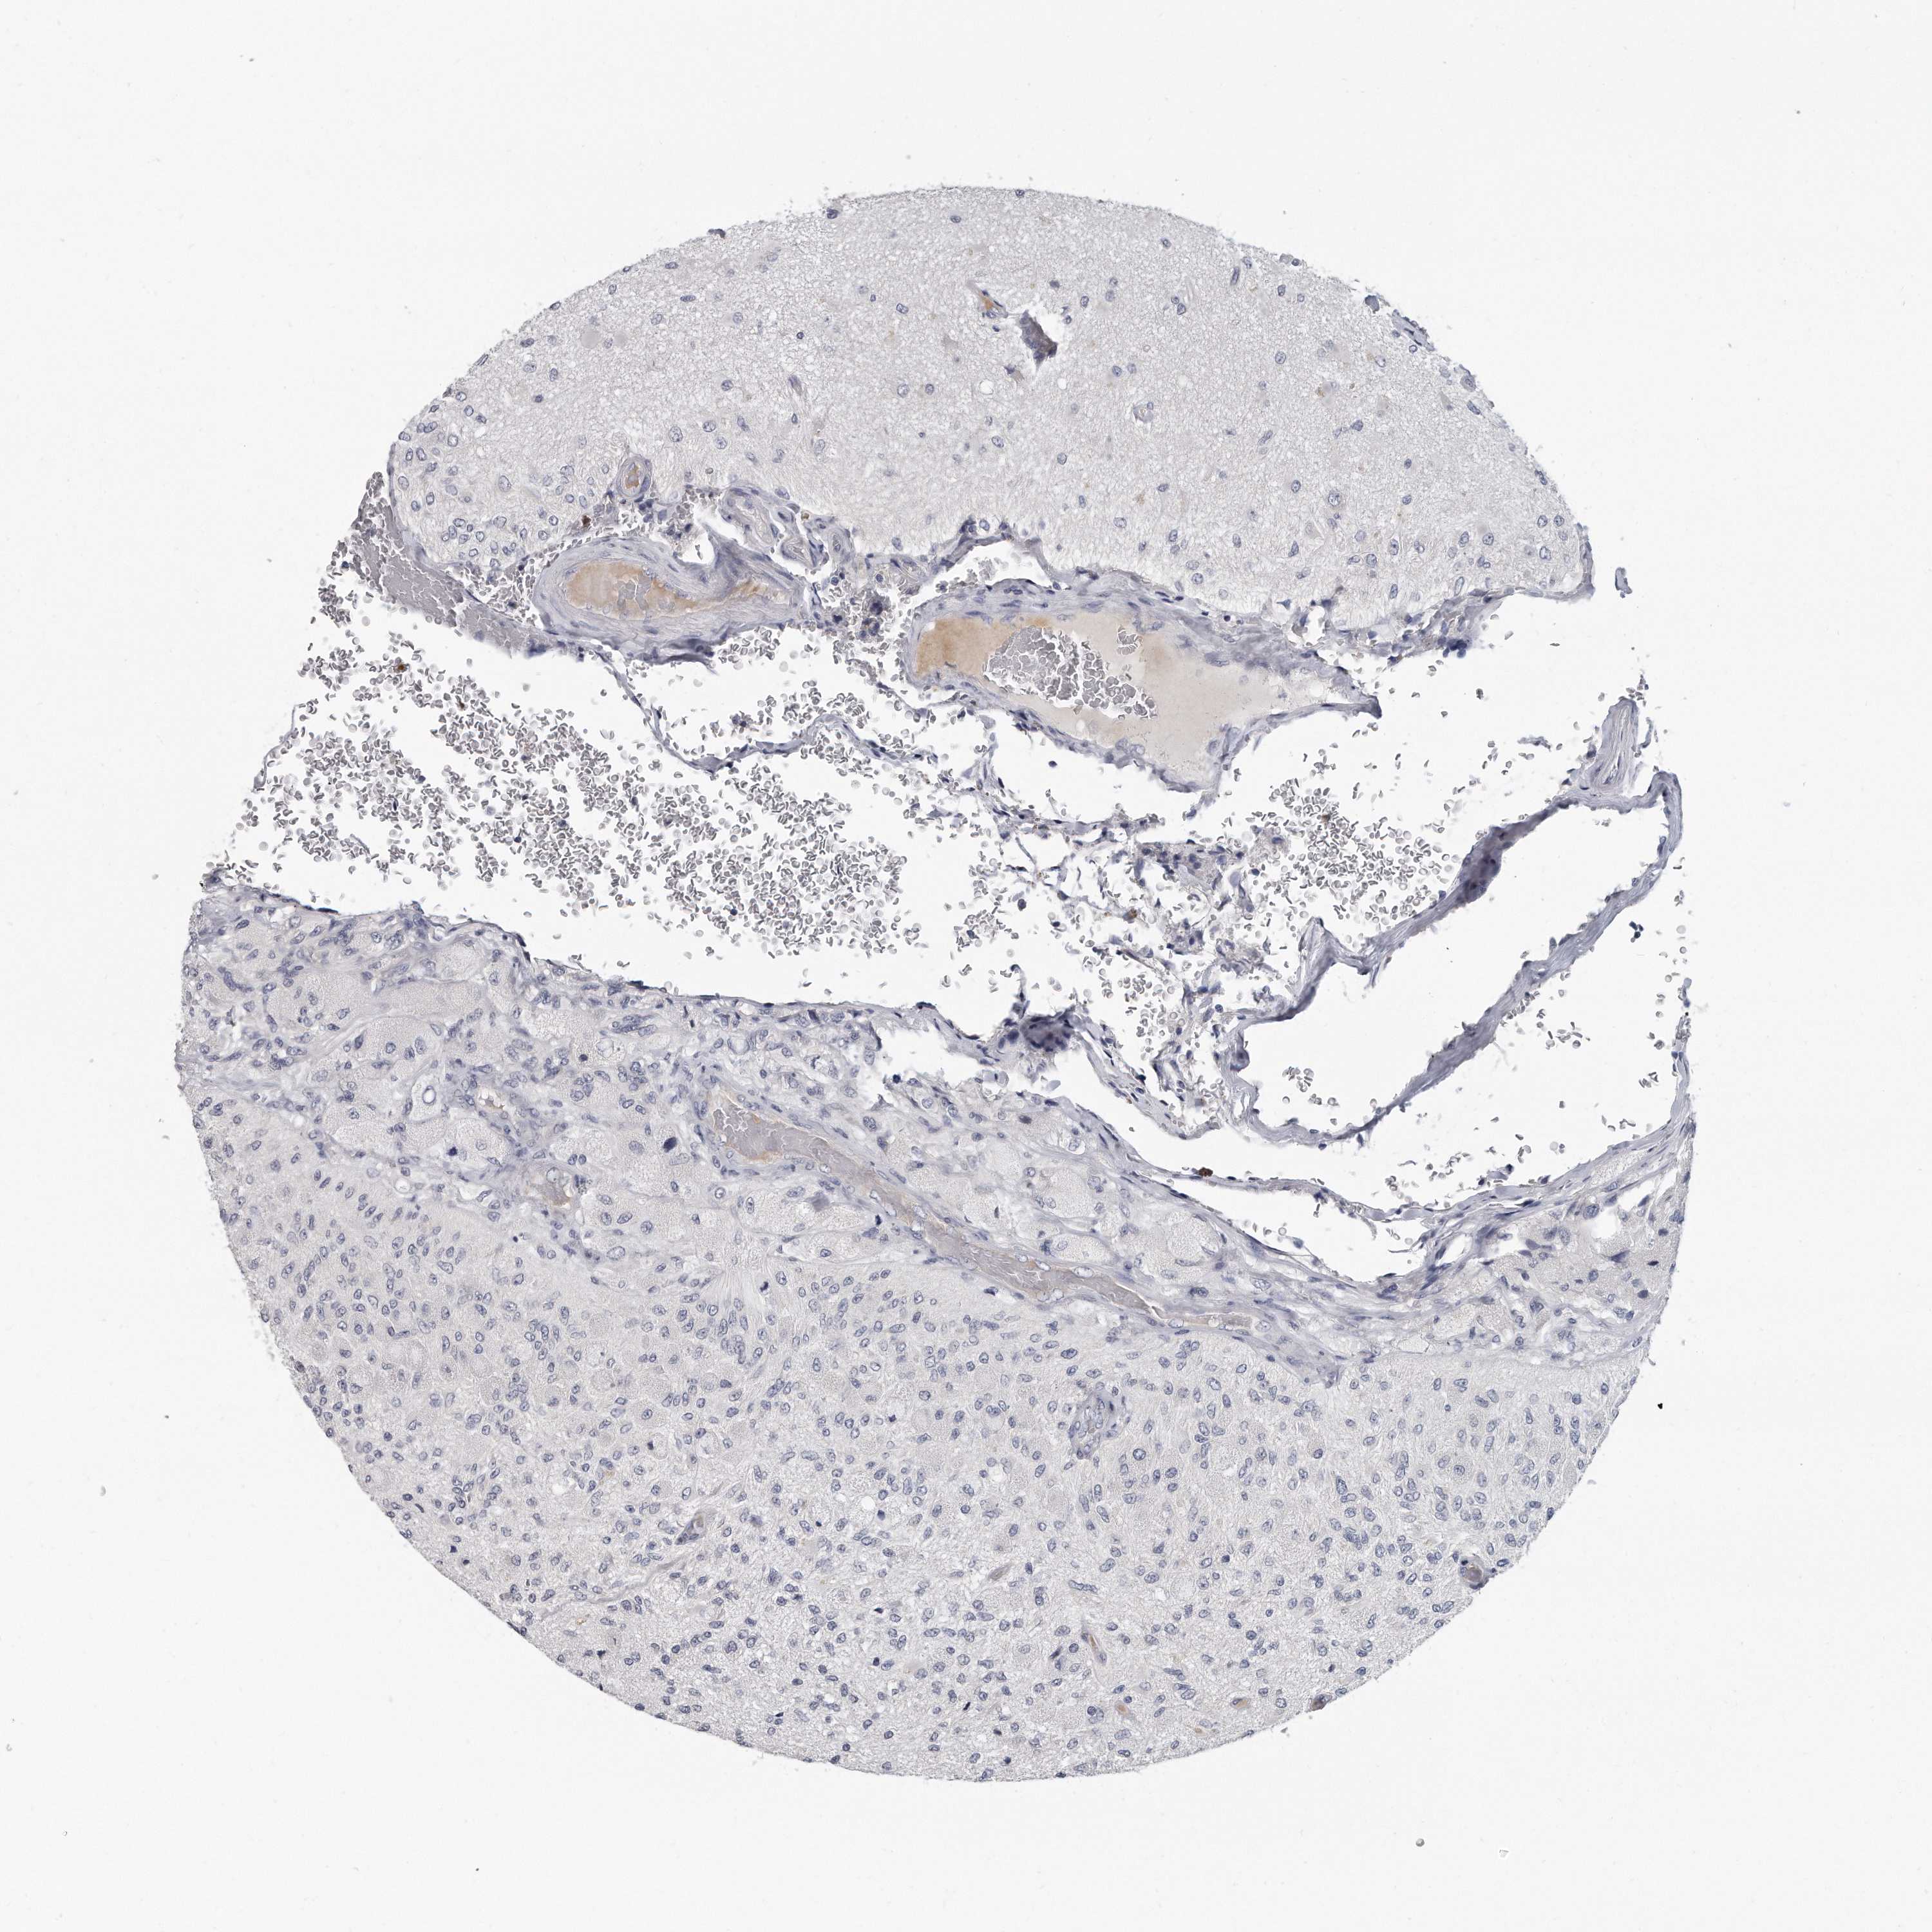

GLIOMA - Protein expressioni

A mouse-over function shows sample information and annotation data. Click on an image to view it in a full screen mode. Samples can be filtered based on level of antibody staining by selecting one or several of the following categories: high, medium, low and not detected. The assay and annotation is described here.

Note that samples used for immunohistochemistry by the Human Protein Atlas do not correspond to samples in the TCGA dataset.

Antibody stainingi

Antibody staining in the annotated cell types in the current human tissue is reported as not detected, low, medium, or high, based on conventional immunohistochemistry profiling in selected tissues. This score is based on the combination of the staining intensity and fraction of stained cells.

Each image is clickable and will lead to virtual microscopy that enables deeper exploration of all samples and also displays staining intensity scores, fraction scores and subcellular localization as well as patient and tissue information for each sample.

Antibody HPA028152

Staining

High

Medium

Low

Not detected

Intensity

Strong

Moderate

Weak

Negative

Quantity

>75%

75%-25%

<25%

None

Location

Nuclear

Cytoplasmic/membranous

Cytoplasmic/membranous,nuclear

Glioma, malignant, High grade

Glioma, malignant, Low grade

Glioblastoma, NOS